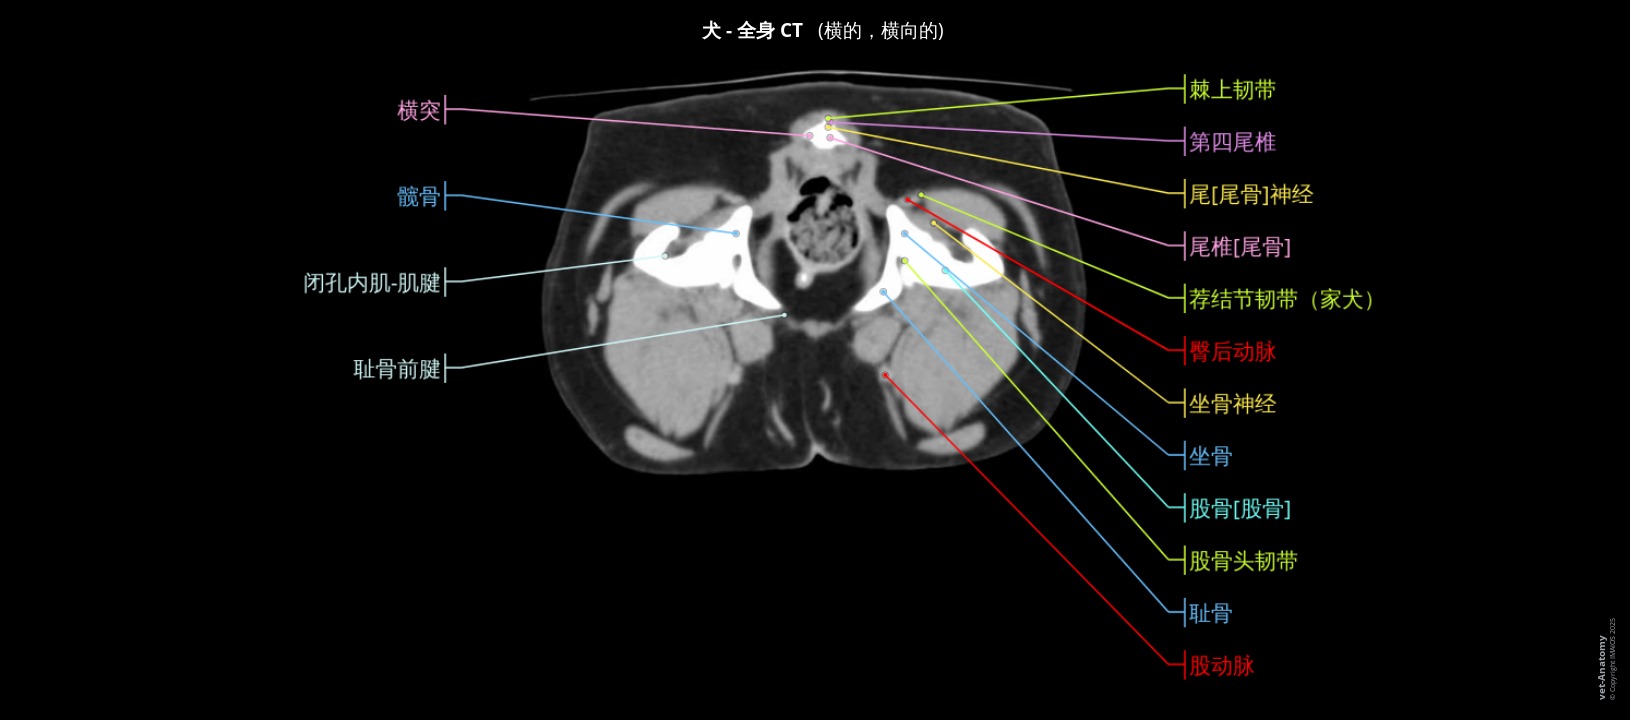

狗全身解剖图

- Antoine MICHEAU, MD

- 发布日期: 2022年2月24日 | 最新更新 2025年11月24日

- https://doi.org/10.37019/vet-anatomy/898995.cn ISSN 2534-5087

简介

横断面解剖学知识在兽医学中是不可或缺的,特别是对于计算机断层扫描(CT、扫描仪)和MRI检查的解释。另一方面,从宏观解剖学到截面解剖学的过渡可能很复杂:此单元被设计为一种教育工具,以帮助初学者(特别是兽医学学生)学习截面放射解剖学。

在此单元中,母狗整个身体的主要解剖结构已在横截面上标注,但未详细说明:可参考其他单元以获取更多信息。

材料与方法

这些绝育母狗的全身图像是由法国(Saint Laurent du Var欧洲兽医诊断成像学院)Delphine Rault医生在注射造影剂后通过计算机断层扫描 (CT, 扫描仪) 所拍摄的。

这些图像是全身横截面和骨骼的3D记录。

IMAIOS兽医解剖学家Stephan Mahler根据国际兽医解剖学名词(NAV)标记了解剖结构。它们被分为不同的主题:

- 身体部分

- 身体区域

- 骨

- 颅骨

- 舌骨器

- 附肢骨骼

- 轴向骨架

- 胸骨

- 肋骨

- 编号-椎骨

- 编号-肋骨

- 关节

- 韧带

- 肌肉

- 消化系统

- 腹膜

- 呼吸系统

- 泌尿器官

- 心脏

- 动脉

- 静脉

- 淋巴系统

- 神经系统

- 感官

- 内分泌腺

备注

该研究是在先前通过卵巢子宫切除术绝育的母狗身上进行的:在这种情况下没有发现卵巢或子宫。

International Committee on Veterinary Gross Anatomical Nomenclature. 2017. Nomina Anatomica Veterinaria. Sixth Edition. Ghent (Belgium).

Evans HE, de Lahunta A. 2013. Evans Miller’s Anatomy of the Dog. Fourth Edition. St Louis (MI): Elsevier Saunders.

Ruberte J, Sautet J. 1998. Atlas d’Anatomie du Chien et du Chat. Barcelone. Multimédica.